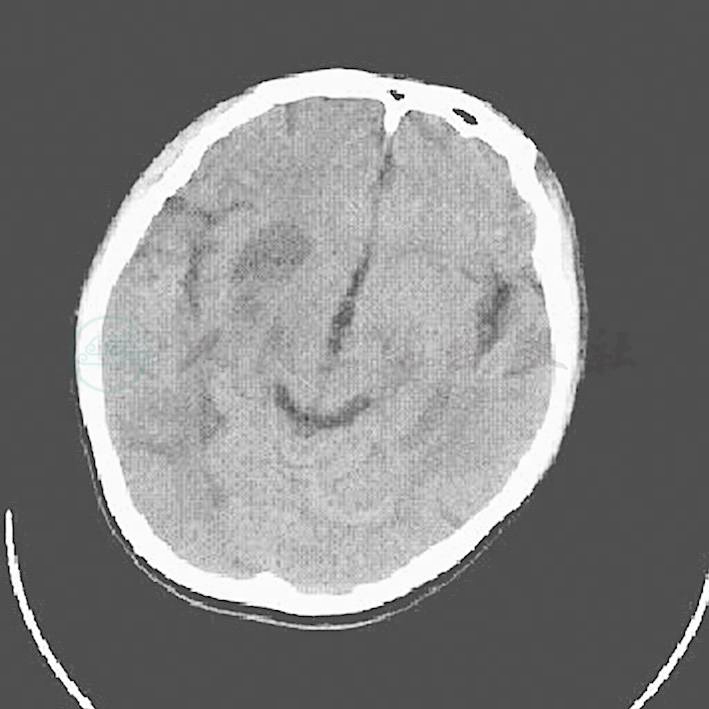

4.3月18日患者仍有头痛,但神志清楚,精神较前明显好转,查体心脏杂音仍存在,肌力同前,复查头颅CT(图3):颅内多发病变,考虑颅内脓肿。为进一步治疗转至普通病房,抗生素方案调正为:万古霉素1g,每12小时1次和青霉素钠960万U,每12小时1次静脉滴注,同时予以甘露醇及甘油果糖每6小时1次静脉滴注脱水治疗,低分子肝素抗凝治疗、3月23日过渡为口服华法林抗凝,前列地尔改善微循环治疗等。

图3 右侧基底节区、侧脑室旁、双侧额顶叶及基底节区见片状低密度灶,右侧脑室受压变窄